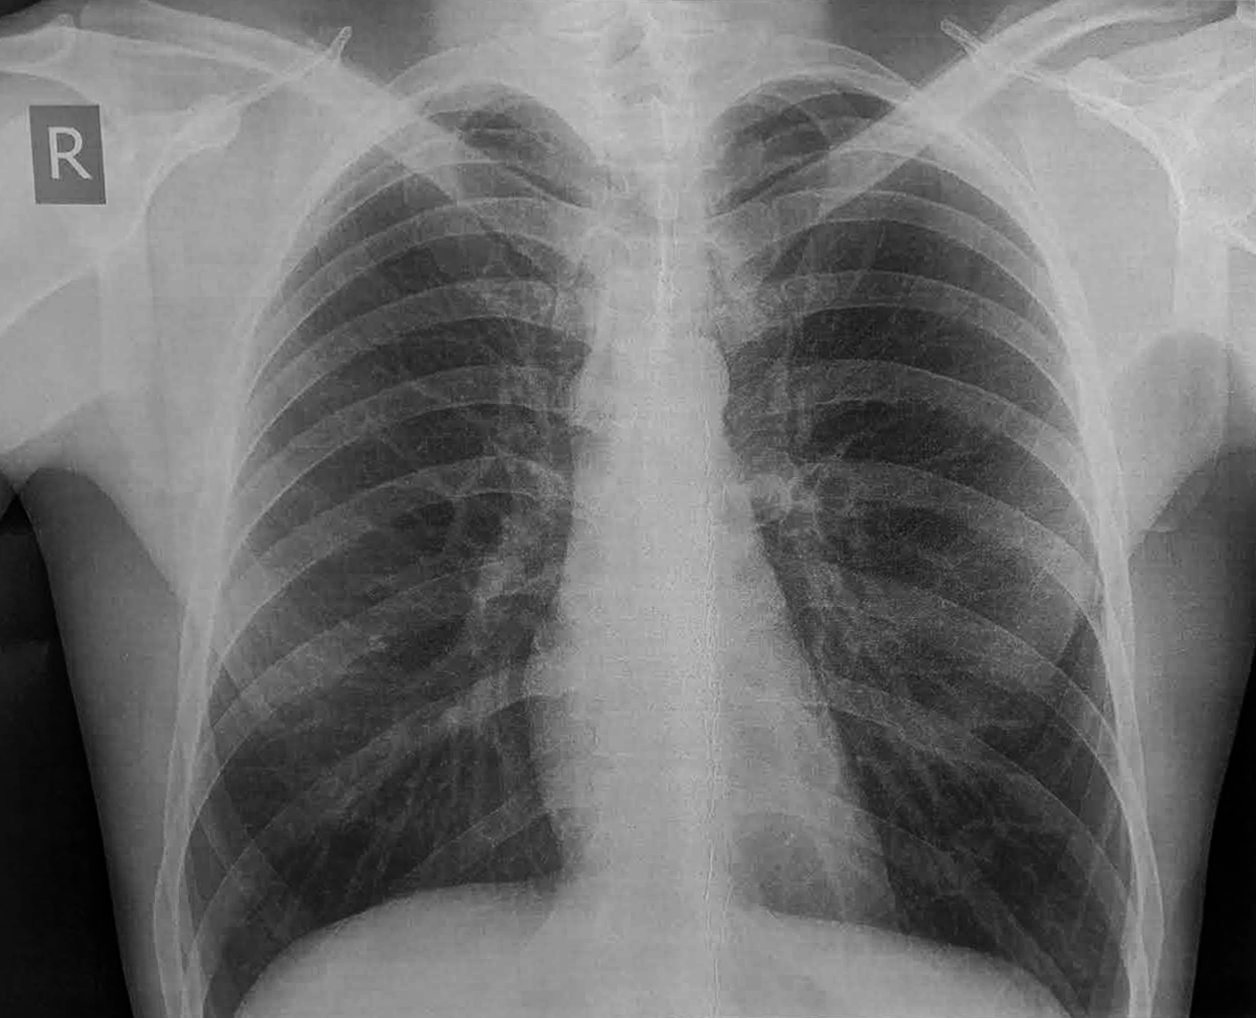

Чоловік 37 років, спортивної статури, доставлений ургентно каретою ШМД із скаргами на загальну слабкість і біль за грудиною середньої інтенсивності. Пульс 80 уд./хв., АТ=110/70 мм рт.ст.

За два дні до госпіталізації виконував інтенсивну фізичну роботу (перевантажував дуже важкий груз), після чого вперше відчув біль в лівому плечі, самостійно приймав НПЗП без значного ефекту. Упродовж двох днів стан погіршувався, - виникла значна слабкість, задишка, з'явився і посилився біль за грудиною. Самостійно звернувся до районної лікарні, де на ЕКГ було виявлено патологічні зміни і хворого ургентно транспортовано в спеціалізоване кардіологічне відділення.

Чому ми не бачимо ЕКГ-ознак залучення в процес ПШ на стандартній ЕКГ? Дійсно, за даними ЕхоКС у пацієнта значно постраждала скоротливість саме правого шлуночка. Зазвичай при такому ураженні ми бачимо елевацію ST V1>V2, елевацію ST в III>II, і характерні зміни в правих відведеннях V3R-V4R. В цьому випадку додаткові праві відведення не були зареєстровані, хоча це б дозволило зробити діагностику більш точною.